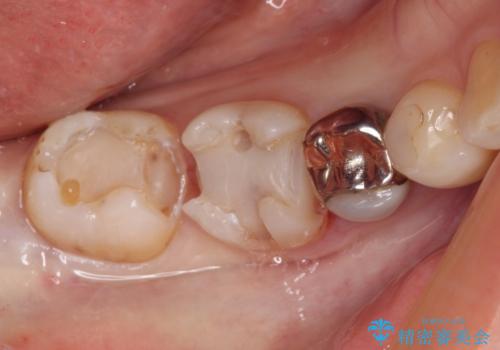

- 奥歯の虫歯を心配して来院した患者様です。

レントゲン写真から、以前治療した詰め物の下に虫歯があることがわかりました。

精度が高く、虫歯の再発リスクの低いゴールドインレーで治療を行うこととしました。